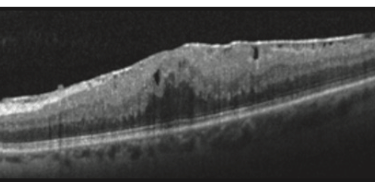

• Tomografia de Coerência Óptica (OCT): Um exame de imagem não invasivo que cria uma seção transversal detalhada da retina, permitindo visualizar a membrana e avaliar sua espessura e impacto na mácula.